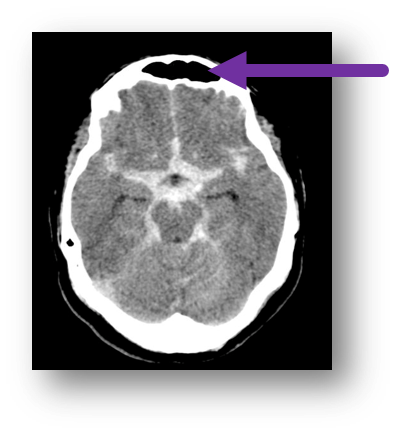

15

Q

A

subarachnoid hemorrhage